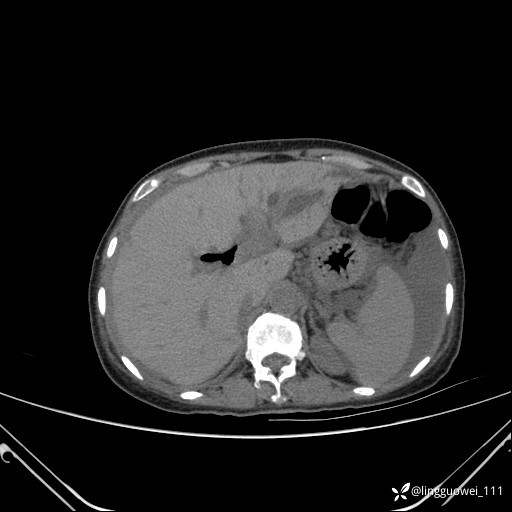

病例女,65岁,门诊行胃肠镜检查后,说腹胀入院检查,CT能发现病因吗?已公布结果

主诉:门诊行胃肠镜检查后,诉腹胀,入院检查,肝有病变吗?腹膜及腹腔的表现有特征性吗?

平扫: